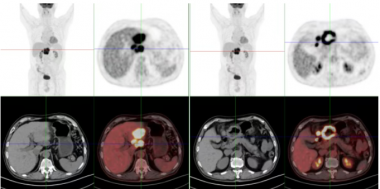

MRI兼容的高性能PET研究及医学应用——中国科学院深圳先进技术研究院研究员柳正